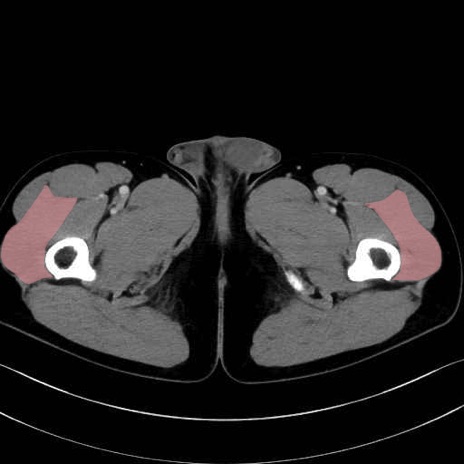

外側広筋(vastus lateralis) のCT画像の解剖

外側広筋 (Vastus lateralis)